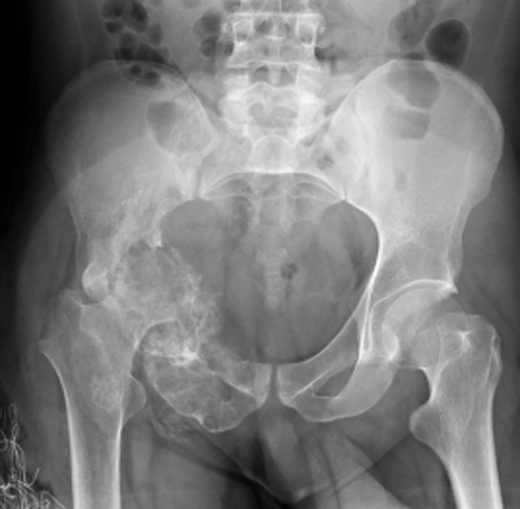

Mientras lo examinaban, los médicos lo encontraron completamente sano, pero el sujeto de 63 años, les dijo que sentía fuertes molestias en el pene. A raíz de esto le realizaron una radiografía pélvica que reveló una extraña y dolorosa condición.

Los rayos X mostraron que su miembro se estaba osificando, esto quiere decir que su miembro genital se estaba convirtiendo en un hueso, condición que sólo ha sido diagnosticada en 40 personas.

Esto ocurre cuando se depositan sales de calcio en los tejidos blandos del órgano, provocando la aparición de placas de hueso donde no debería haber. Esta placa se endurece y reduce la flexibilidad, además de provocar una curvatura durante la erección, lo que provoca disfunción eréctil.

Según un artículo en la revista científica Urology Case Reports, esta condición está relacionada con la enfermedad de La Peyronie o induración plástica del pene.